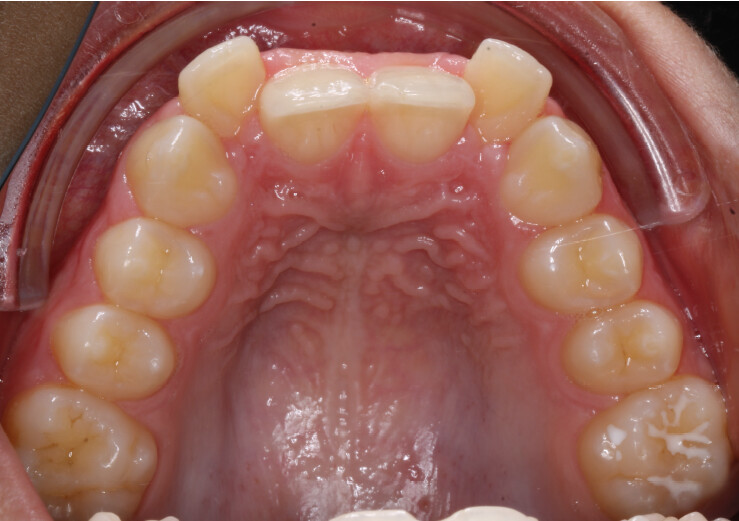

Chief complaint: The patient’s primary concerns were the gummy smile associated with a deep bite, and the limited space available for anterior alignment. He also expressed dissatisfaction with the position of the maxillary lateral incisors, describing them as being positioned “too high.”

A 13-year-old male patient presented with a deep bite, characterized by near-complete coverage of the mandibular incisors. Clinical evaluation revealed bi-arch crowding, dental rotations, and proclination of the maxillary lateral incisors, contributing to the patient’s esthetic concerns. The facial profile was retrusive, consistent with mandibular retrognathism, and no significant periodontal abnormalities were detected.

The patient presented with a skeletal Class II relationship with bilateral molar and canine Class II and a Class II division 2 dental pattern. The deep bite was associated with anteroinferior crowding and an accentuated Curve of Spee. Facial analysis revealed good symmetry, a slightly increased lower facial third, and a convex profile characterized by mandibular and chin retrusion. Lip competence was mildly reduced, with a decreased nasolabial angle and mentalis hyperactivity, all of which compromised overall facial harmony.